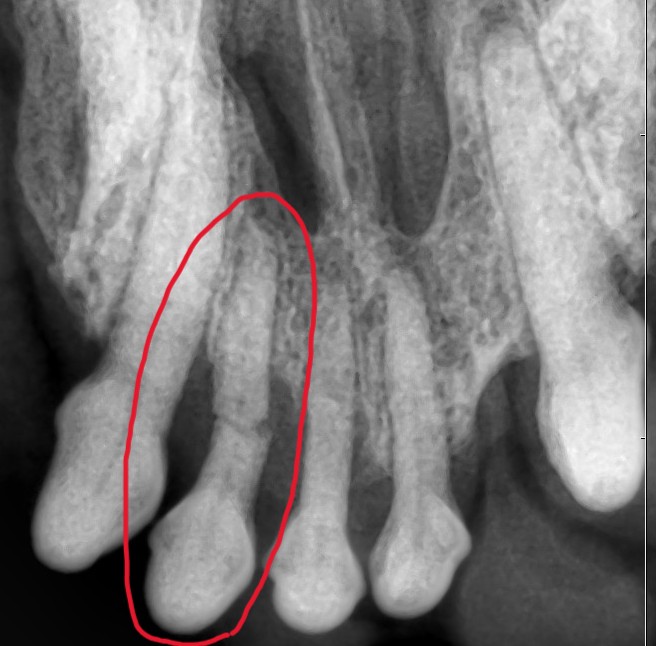

こんにちは! 世田谷区等々力にあります、けいこくの森動物病院です🌳 今回は11才の🐶ミニチュア・シュナウザーちゃんの歯科処置についてご紹介いたします。 来院された理由 来院された理由は【歯のぐらつきと口臭が気になる】ということでした。 診察 最初は触診・視診を行わせていただき、麻酔をかけ…